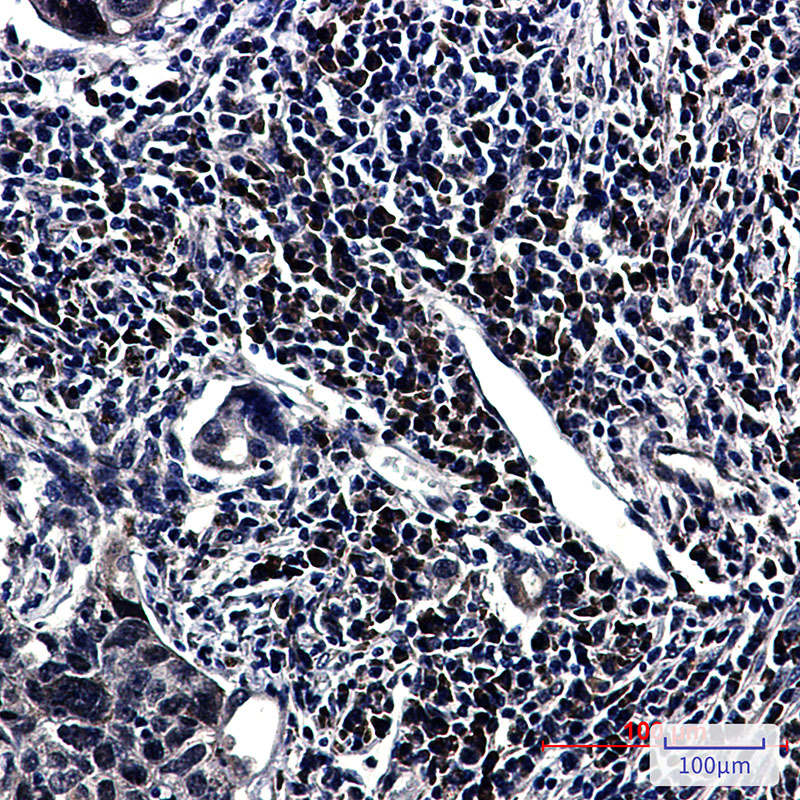

- Immunohistochemistry analysis of paraffin-embedded Human lung cancer tissue using E1BAP5 antibody.High-pressure and temperature Sodium Citrate pH 6.0 was used for antigen retrieval.